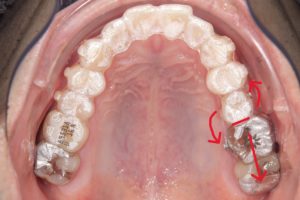

左上第二小臼歯頬側を赤い線で示す。

回転が必要な歯とその前後の歯にボタンを付与し

パワーチェーンを併用して補助的な力を加える。

並行してマウスピースによる遠心移動を行い、

回転するスペースを確保する。

4カ月経過した口腔内

「装置任せ」にしたり、「マウスピースではできない」と判断するのではなく、

歯の形態、骨の条件、力の方向を分析した上で、

必要な補助を組み合わせることで

これまでマウスピースでは難しいとされていた動きの達成率を高めています。